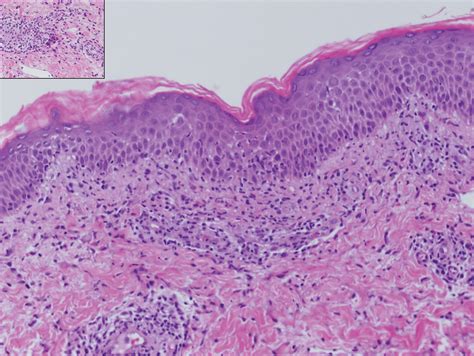

• Angiokeratomas: These are small, non-cancerous clusters of blood vessels that appear as dark red, purple, or black spots. They are very common as men age and are generally harmless.